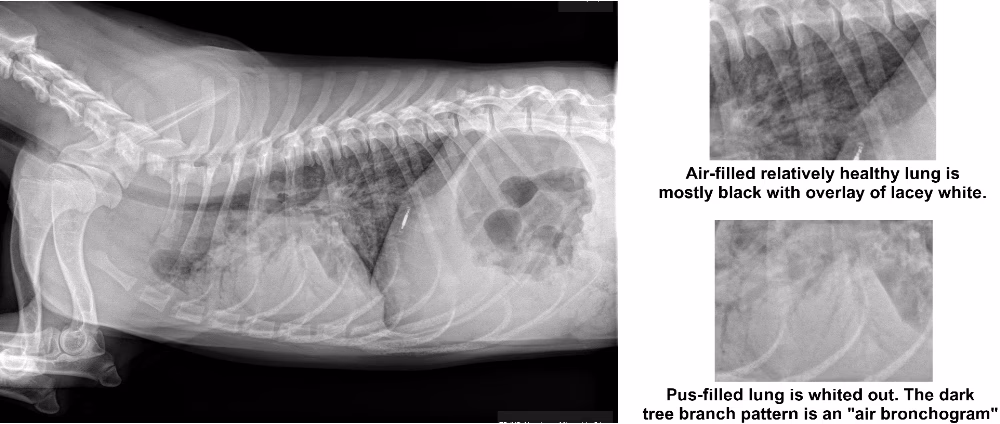

Diagnosen stilles typisk på baggrund af en kombination af den kliniske undersøgelse, sygehistorien og vigtigst af alt, røntgenbilleder af brystkassen. Røntgenbilleder kan vise de karakteristiske forandringer i lungerne, der indikerer væske- og pusansamling.